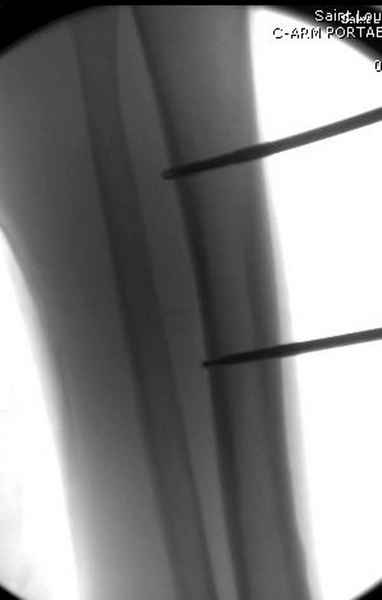

Больному с политравмой установлен наружный "spanning-bridging" фиксатор, после нескольких Irrigation&Debridment на фоне отрицательного посева из раны, через открытый участок установлен 4.5 mm Locking Plate.

На фоне фиксированного перелома бедра мероприятия по восстановлению мягкотканого покрова. Перелом голени зафиксирован после стабилизации бедра традиционным методом.